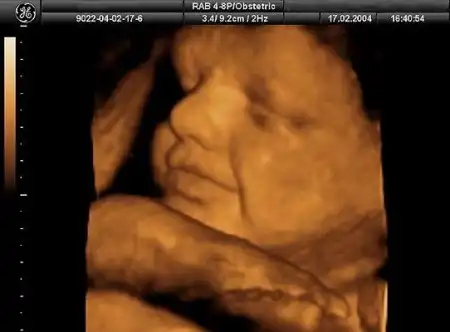

У мамы в животике)